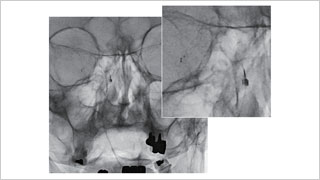

日本医科大学 脑神经外科,博慈会纪念综合医院 脑神经外科

佐藤 俊